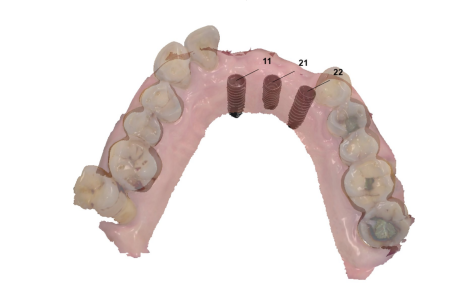

3.拔牙與骨釘:為騰出空間進行矯正,需要拔牙;骨釘用於輔助移動牙齒,初期可能會有異物感,但通常很快能適應。(下兩圖)

拔牙後放骨釘關閉空間原理與優點:

1.骨釘是植入在骨頭中的支撐點,提供穩定的錨定力量,確保牙齒移動的方向不受影響。

2.傳統矯正中移動牙齒可能造成其他牙齒跟著移動,使用骨釘可以精準控制牙齒的移動方向,讓拔牙後的縫隙能有效且正確地關閉。

3.骨釘可以大幅提升牙齒移動的效率,可能縮短矯正療程時間。

4.除了關閉拔牙空間,骨釘還能應用於骨性暴牙、嚴重深咬等情況,讓治療範圍更廣。